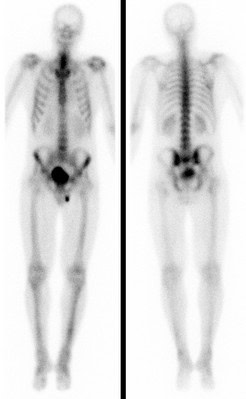

Bei der Skelettszintigraphie werden schwach radioaktiv markierte Phosphatkomplexe verabreicht, die zunächst im Blut durch den Körper zirkulieren und im Verlauf von 2-3 Stunden ausreichend in den Knochen eingebaut werden, so dass dann der Knochenstoffwechsel abgebildet werden kann.

Es bestehen die Möglichkeiten, gleich nach Verabreichung der Phosphatkomplexe die Durchblutung zu untersuchen und auf den Spätaufnahmen den Knochenumbau zu beurteilen. Bei der Skelettszintigraphie gibt es keine Unverträglichkeitsreaktionen auf die verabreichten Radiopharmaka. Im Gegensatz zu vielen Röntgenkontrastmitteln sind die verwendeten Radiopharmaka auch nicht nierenschädlich.

Die Hauptfragestellungen bei der Skelettszintigraphie betreffen die Feststellung evtl. Knochenmetastasen bei Krebserkrankungen und die Unterscheidung von primär entzündlichen vs. primär degenerativen Gelenkerkrankungen, also rheumatischen Grunderkrankungen mit Skelettbeteiligung vs. (aktivierten) Arthrosen.

Darüber hinaus ist die Skelettszintigraphie häufig auch bei der Abklärung unklarer Knochenschmerzen sehr hilfreich, etwa zur Feststellung evtl. Knochentumoren, von Prothesenlockerungen, einer Osteomyelitis, von Frakturen, von Knocheninfarkten etc.